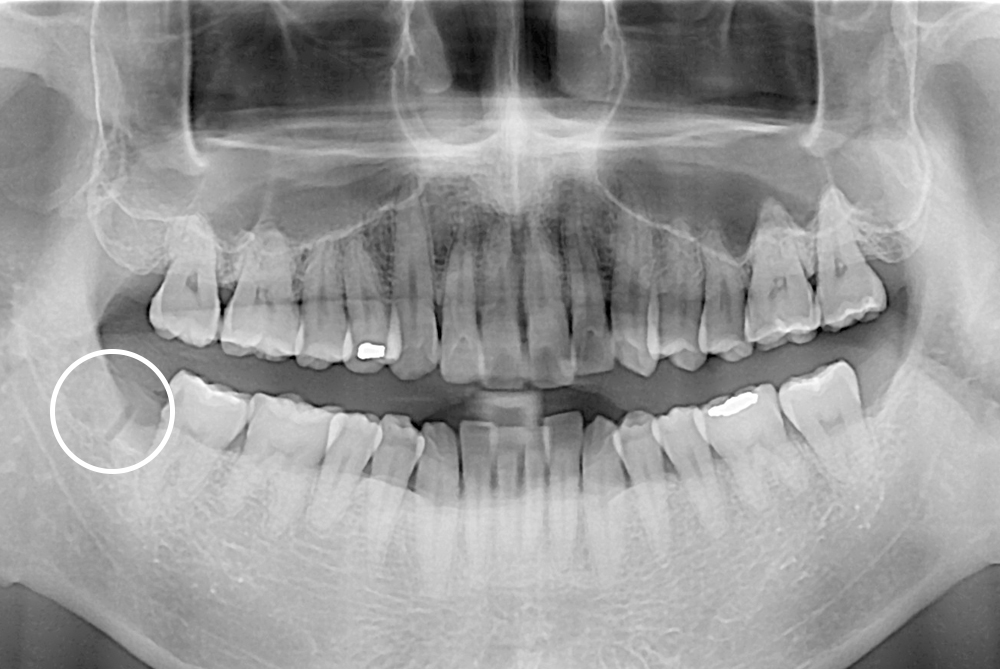

[사랑니] 매복 사랑니 발치

치료전 : 2018-08-07

세종치과는 구강악안면외과학 박사이신 원장님이 발치하는 치과입니다.